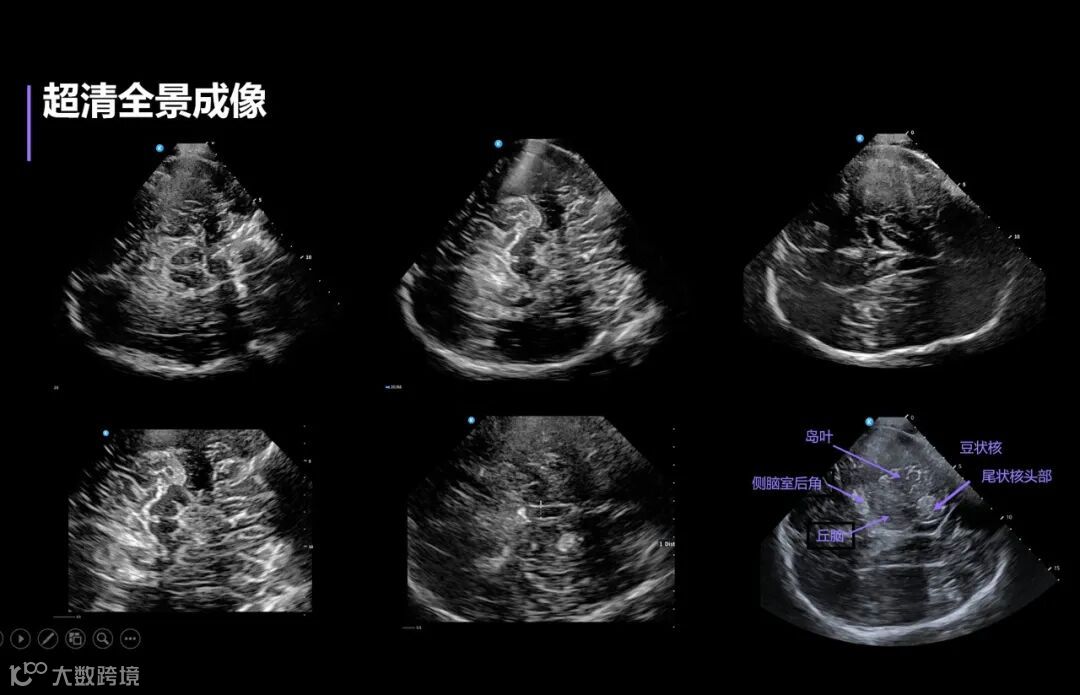

传统超声在颅脑应用领域受限于颅骨屏障,鲲为科技独创的kOS成像平台,运用独特的全模态平面波、SRBF超分辨波束合成以及UP超穿探头,依托于强大的GPU处理能力,在业内首次实现了超高穿透力与深部分辨率的完美结合,得到了深部超分辨图像,开启超分辨超声新时代。

鲲为临床专家在会上首次发布“颅脑超声临床解决方案”,并通过动态影像展示了这项创新性技术在颅脑神经疾病中的临床应用价值。

该方案为神经退行性病变如帕金森病的早期诊断和鉴别诊断、急性出血性卒中评估、脑血管病的筛查等提供了全新临床应用场景,颅脑超声的应用必将推动急诊卒中筛查、神经疾病等临床场景的诊疗革新。